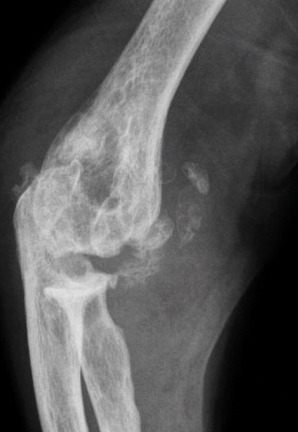

Le patient non traité par hypo-uricémiant peut développer une goutte polyarticulaire chronique caractérisée par des articulations douloureuses et gonflées en permanence, l’apparition de tophus (fig. 1) voire d’une arthropathie destructrice (fig. 2 et 3), et des manifestations rénales (lithiase rénale, le plus souvent uratique, néphropathie interstitielle …).

La forme pseudorhumatoïde est rare (5 %), simulant une polyarthrite rhumatoïde (diagnostic différentiel), avec parfois des signes systémiques d’inflammation (élévation de la vitesse de sédimentation et de la CRP). Le diagnostic repose sur la mise en évidence des cristaux de PPC. La radio peut mettre en évidence des calcifications des cartilages articulaires (fig. 6) et des fibrocartilages (fig. 7, 8, 9 et 10). L’échographie (plus sensible) peut mettre en évidence des dépôts de PPC, qui apparaissent comme une fine bande hyperéchogène au sein des cartilages hyalins et comme des points scintillants dans les fibrocartilages ou dans la membrane synoviale. Dans l’arthrite chronique à PPC, lespossibilités thérapeutiques sont, par ordre de préférence : colchicine (de 0,5 à 1 mg/j), petites doses de cortisone, parfois les AINS per os (mais leur prescription est souvent limitée par les comorbidités chez les patients âgés), méthotrexate et l’hydroxychloroquine. Il n’y a pas aujourd’hui de traitement « de fond », mais des molécules sont à l’étude.

L’arthrose associée aux dépôts de PPC touche en particulier les genoux, avec une symptomatologie chronique et/ou des accès aigus cristallins. Par comparaison avec l’arthrose idiopathique, elle serait à l’origine d’une symptomatologie plus inflammatoire, toucherait des articulations inhabituelles (radiocarpienne, carpienne, gléno-humérale, médio-pied et arrière-pied, cheville) et serait associée à plus d’ostéophytes et de géodes. Cette arthropathie dégénérative peut s’accompagner de lésions structurales sévères avec disparition rapide de l’interligne (arthropathies destructrices : hanches, genoux, poignets, coudes). Les objectifs et les modalités thérapeutiques sont identiques à ceux d’une arthrose idiopathique. Aucun traitement ne permet la dissolution des cristaux de PPC.